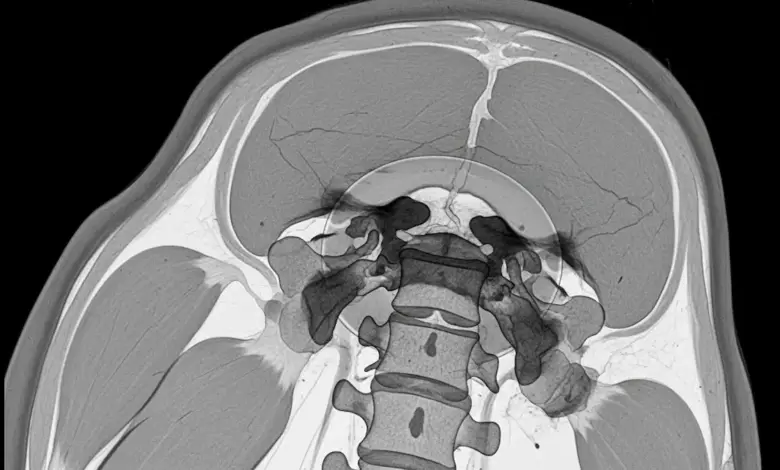

Na imagem, a ressonância magnética é o exame mais sensível para detectar inflamação do disco e das vértebras, além de avaliar abscessos e compressão de estruturas neurais.

O acompanhamento costuma usar avaliação clínica e queda progressiva de PCR e VHS. Controle por imagem pode ser indicado em casos selecionados, principalmente quando há piora clínica, suspeita de abscesso ou sintomas neurológicos.